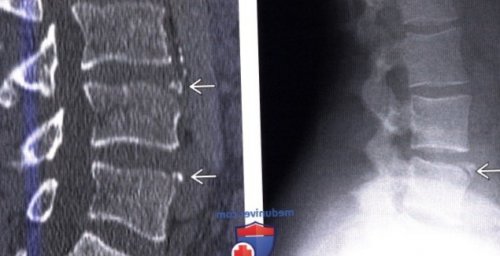

(Слева) Рентгенограмма в боковой

(Справа) КТ, сагиттальная проекция: типичные фрагменты limbus

проекции: типичный limbus vertebra